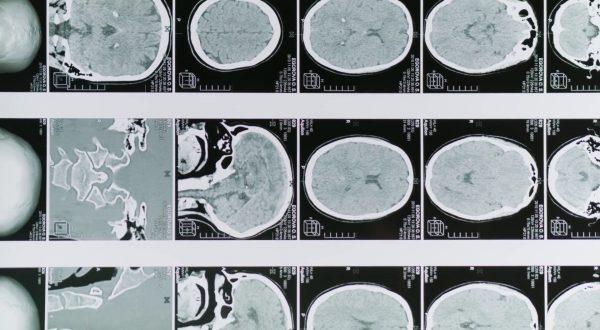

Glioblastoma, le molecole naturali migliorano la chemioterapia